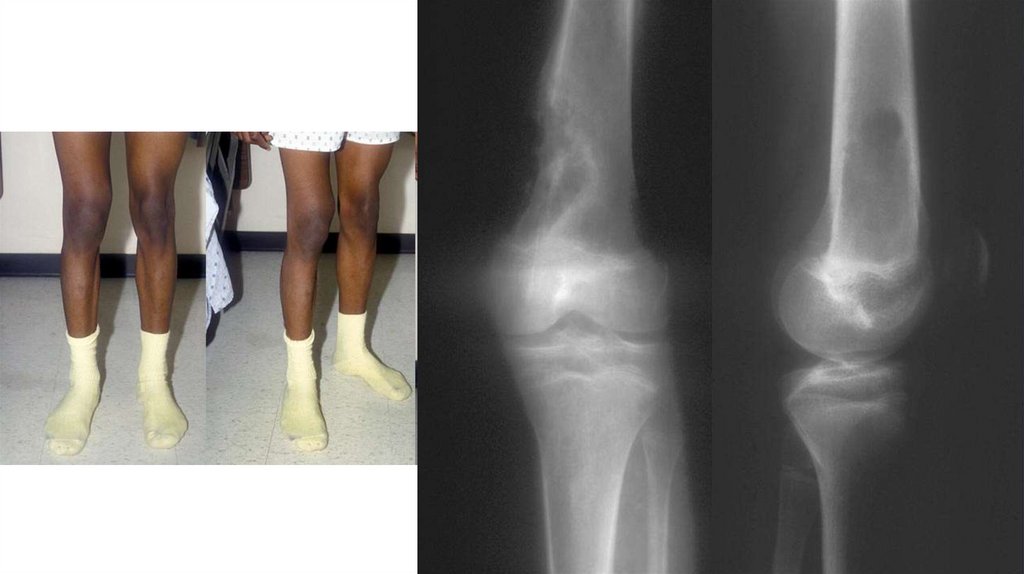

Диагностика

• Рентгенография (очаг деструкции, игольчатый периостит,

«козырек» Кодмана)

• КТ

• МРТ с контрастированием

• Сцинтиграфия с технецием

• Биопсия (высокий полиморфизм с наличием большого количества

митозов, наличие новообразованных остеоидных структур)

• Поиск метастазов